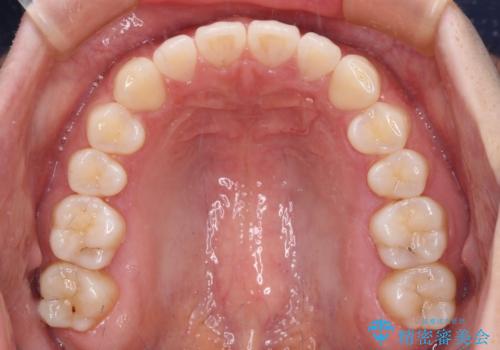

すきっ歯とオープンバイト インビザライン・ライトで改善

すきっ歯程度の軽度の歯列不正であったため、インビザライン・ライトにより咬合改善を行うこととしました。

オープンバイトやすきっ歯は、舌突出癖によりあっという間に後戻りをするため、矯正治療前からトレーニングを行っていただき、更には後戻り防止のワイヤーリテーナーを併用しています。